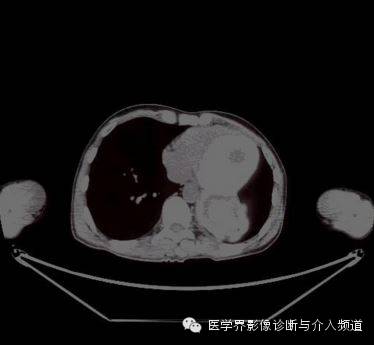

胸片示左下胸腔一肿块影。CT增强示左肺下叶一低密度肿块,其内可见高密度影,PET-CT示肿块边缘FDG摄取增加,肿块中央摄取减低。

异物性囊肿或脓肿是由于纱布引起的周围组织 、器官的慢性炎性反应,出现渗出、液化坏死并纤维包裹所形成的囊肿或脓肿,周围有假性纤维包膜或较厚的壁,CT 表现为囊性为主的混杂密度块影,壁较光滑,其内出现云雾状、漩涡状或脑回状密度增高影漂浮于其中,增强后亦表现为壁强化,内容物无强化。部分学者报道,纱布瘤内部出现气泡及边缘出现钙化是其重要特征之一。

综上所述,发生于胸腔或腹腔的肿块,具有良性病变的实性或囊性占位特征,肿块内部可见云雾状或漩涡状稍高密度影,可以出现边缘钙化,增强后壁强化,内容物无强化,再结合患者既往有手术病史,应首先考虑腹腔或胸腔纱布瘤。